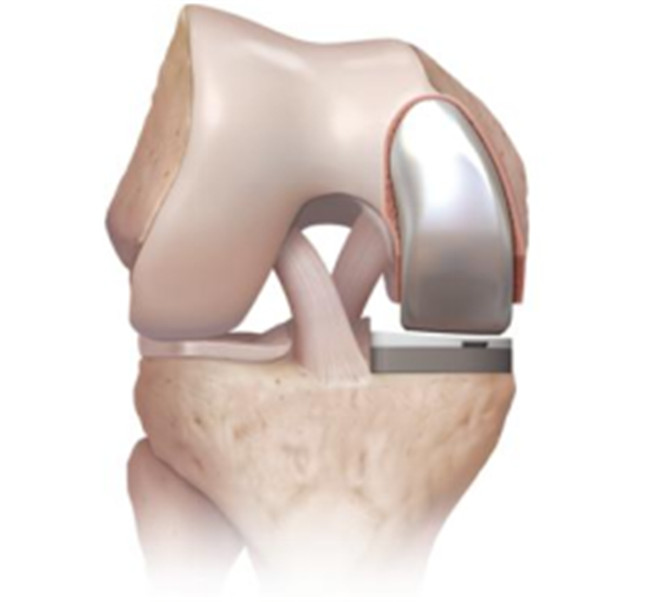

對于全膝關節(jié)置換術而言,膝關節(jié)單髁置換術是相對微創(chuàng)手術,精準置換病損部位,用以替代膝關節(jié)股、脛關節(jié)損壞的軟骨表面和半月板,被稱為膝關節(jié)置換中的“補牙技術”,不需要去除前后交叉韌帶,最大限度保留病人的本體感覺和關節(jié)功能,實現(xiàn)膝關節(jié)置換手術的生理性重建。膝關節(jié)單髁置換手術具有損傷小、術后恢復快、手術外表美觀和住院時間短等優(yōu)點,是治療膝關節(jié)骨關節(jié)炎的理想辦法。目前,單髁置換技術是關節(jié)外科發(fā)展方向之一,隨著手術器械的發(fā)展和認識水平的提高,單髁置換術在臨床將會擁有廣泛的應用前景。

羅軍主任表示:膝關節(jié)單髁置換術(unicompartmental kneearthroplasty, UKA)是相對全膝關節(jié)置換術而言的一種新型微創(chuàng)手術,切口僅為原來的一半,且能最大限度地保留患者正常的關節(jié)部分,對患者的損傷更小,術后療效更佳,是骨性關節(jié)炎患者的一大福音。